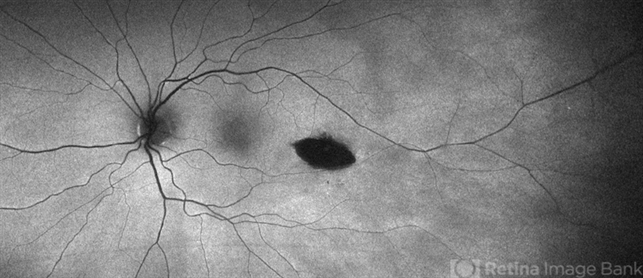

- maculopathy, torpedo maculopathy, macula, Optos, autofluorescence imaging

- Optos Ultra-Widefield Autoflurescence Imaging

- Optos fundus autofluorescence photograph of a 35-year-old asymptomatic female with no ocular or medical history with stable and chronic appearing torpedo-shaped macula lesion in the left eye.